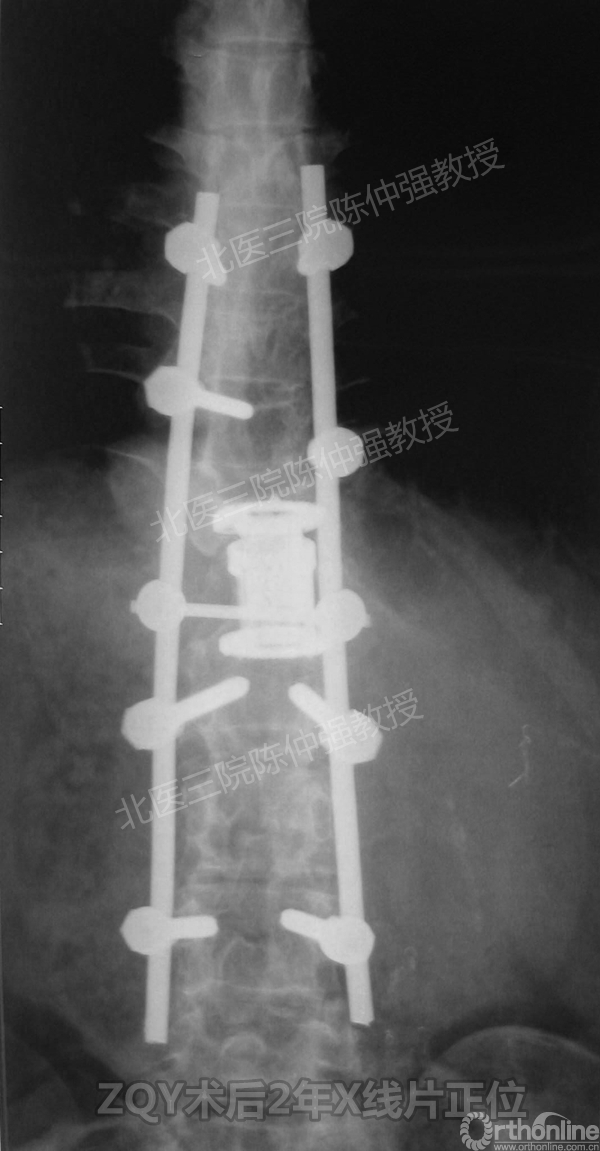

ZQY术后2年

患者女性17岁,胸腰椎陈旧结核性侧后凸畸形,局部呈“麻花状”扭转,无神经功能受损表现。2005年,陈仲强教授带领团队实施后路+侧前方联合入路脊柱节段切除、双轴旋转矫形术。术后患者外观显著改善,神经功能正常。术后随访证实患者截骨矫形节段骨性融合良好,矫形效果持续良好。